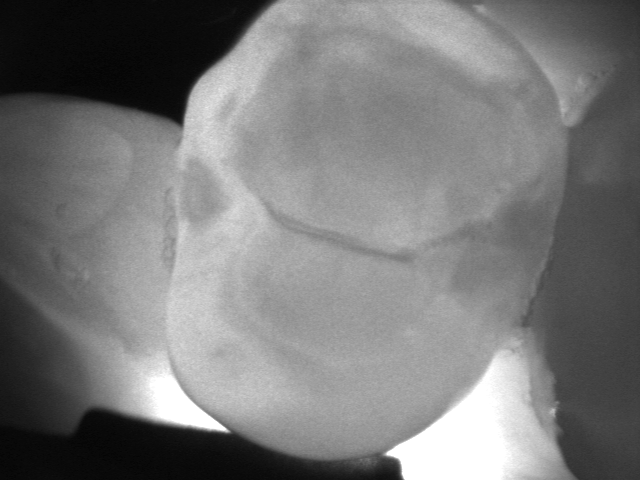

La videocamera digitale sulla testa del manipolo rileva luci ed ombre all’interno del dente e proietta l’immagine ottenuta sullo schermo del pc in tempo reale: le parti sane, che consentono il passaggio della luce, risultano chiare, quelle lesionate, che al contrario lo bloccano, si distinguono nettamente come aree scure.

Le immagini in bianco e nero, altamente dettagliate, ricordano molto le radiografie ma di fatto sono state del tutto ottenute senza radiazioni, soltanto per transilluminazione laser!

Vedere l’estensione della lesione, se ancora soltanto sullo smalto o già sconfinata in dentina, e la sua esatta posizione sono informazioni fondamentali per impostare una terapia che sia il più possibile conservativa.

Consente la diagnosi precoce di cracks (incrinature, fratture), demineralizzazioni e carie (occlusale, prossimale o secondaria sotto vecchi restauri), quando sono sopragengivali.

Evidenzia la carie con più sensibilità e attendibilità della sola ispezione visiva e molto prima che appaia alle radiografie, rendendo possibili trattamenti profilattici o minimamente invasivi.